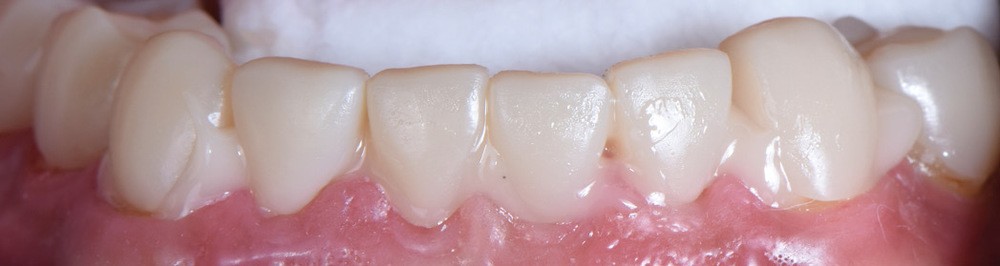

Au vu du contexte para-fonctionnel et de l’étendue de la perte tissulaire, des coiffes périphériques minimalement invasives ont été choisies afin de restaurer l’esthétique et la fonction. Actuellement, aucun consensus n’est fait sur le choix du matériau d’infrastructure à privilégier. Les matériaux hybrides usinables présentent des propriétés mécaniques, physiques et biologiques intéressantes en contexte d’usure sévère (e.g., module d’élasticité, résistance à la propagation de fêlures, facilité de réintervention). Une réhabilitation globale avec remontée de dimension verticale d’occlusion (DVO) par l’intermédiaire de coiffes composites renforcés en nano-céramiques est décrite.